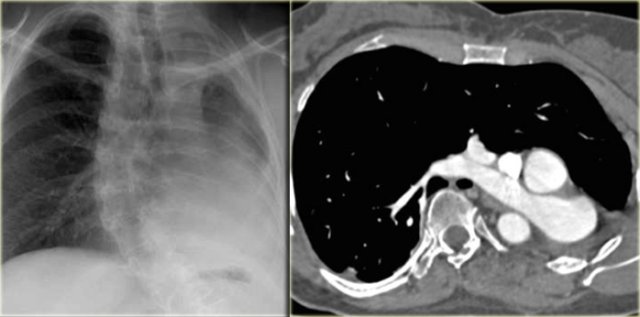

On the left a chest film of a 6-month old boy with stridor and cough.

The trachea is deviated to the left, otherwise the chest film is normal.

So there is some mass effect on the right side.

On the left the reconstructions demonstrating a double aortic arch.

There are branches coming off the right arch and branches coming off the left arch.

Double Aortic Arch Double Aortic Arch

The right arch is typically larger and higher than the left.

There is a complete ring that encircles the esophagus and the trachea and usually there is stridor or dysphagia.

Two brachiocephalic arteries arise on each side separately (four vessel sign).

On the left a chest film of a young adult with a cough.

There is a right paratracheal mass.

The differential diagnosis is tumor, adenopathy or vessel (right arch, dilated azygos vein, dilated aberrant right subclavian artery).

On the left axial images and posterior view of volume rendered reconstruction.

Describe the findings and then continue.

The findings are:

1. four vessel sign

2. double arch

3. right arch higher and larger

4. esophagus and trachea are completely encircled

The narrowing of the trachea is seen on the axial images, but better appreciated on the MPR and Volume Rendered image.